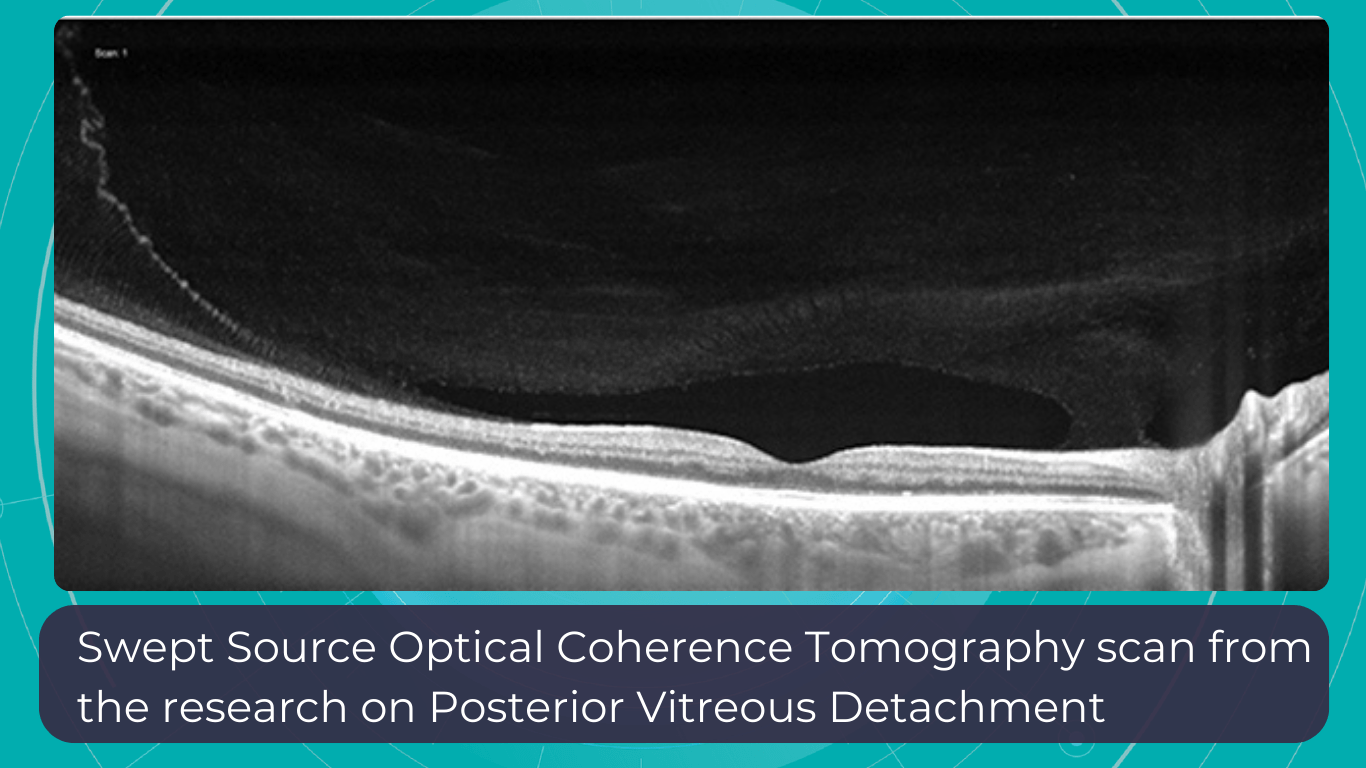

Optometry Technology: SS-OCT

Like SD-OCT, swept-source OCT (SS-OCT) utilizes Fourier domain technology to optimize higher-quality wavelength transduction within the frequency domain. This enables rapid sweeping scan patterns across a broad bandwidth.

However, instead of a broad-bandwidth light source projected all at once, as in SD-OCT, SS-OCT employs a single tunable laser that sweeps through different frequencies to cover the entire spectrum swiftly. The light reflected from the eye is captured by a photodetector significantly faster than the charge-coupled device (CCD) camera used in SD-OCTs. This difference translates to a faster scanning speed of up to 400,000 axial scans per second, eliminating the typical depth-dependent signal drop-off associated with SD-OCT. Additionally, the faster scanning speed reduces image distortions caused by eye movements and allows for wider B-scans, facilitating widefield imaging.

Furthermore, many SS-OCT systems utilize a light source centered at an approximately 1050 nm wavelength, providing better tissue penetration than SD-OCT. This allows for visualization of structures like the choroid, lamina cribrosa, and structures at the anterior chamber angle. This enhanced penetration is crucial in diseases like Central Serous Chorioretinopathy, where evaluating the entire thickness of the choroid can be challenging.

Moreover, volumetric analysis of the choroid and various pathological features can aid in monitoring the progression of Wet AMD, CSCR, and Diabetic Retinopathy, as well as assessing the response to treatments such as anti-VEGF agents, laser photocoagulation, and photodynamic therapy (PDT).